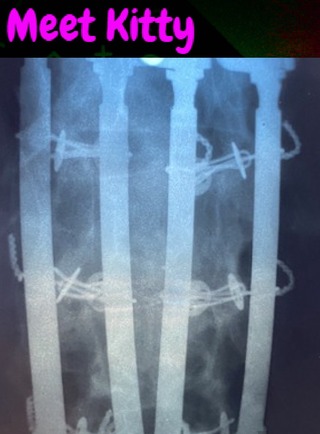

I’m a proud Texan whose military life took me all over the world. These days, I’m fighting—and winning—the battle against Multiple Sclerosis. After several surgeries and four 12-inch metal rods in my back, I’m still here, still gaming, and still unstoppable. 💪